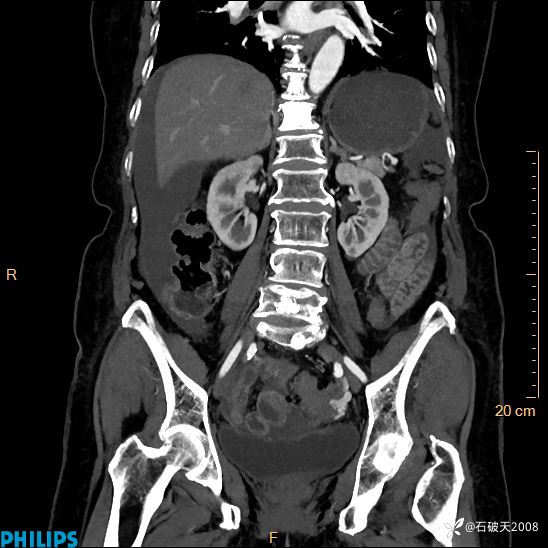

MIP